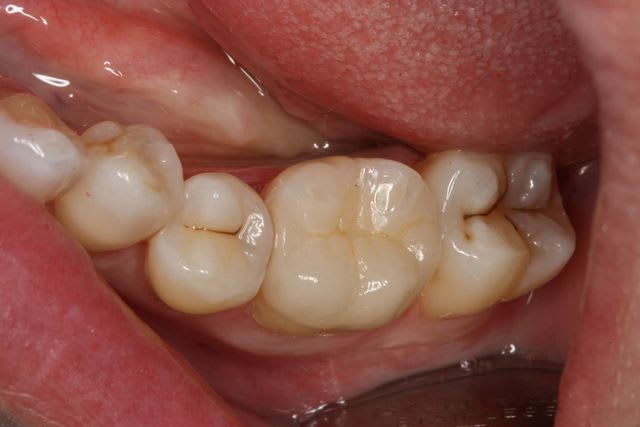

Un petit onlay du dimanche dernier qui m'a fait plaisir. A souligner le travail du prothésiste, content de son boulot après avoir vu les photos.

un autre....